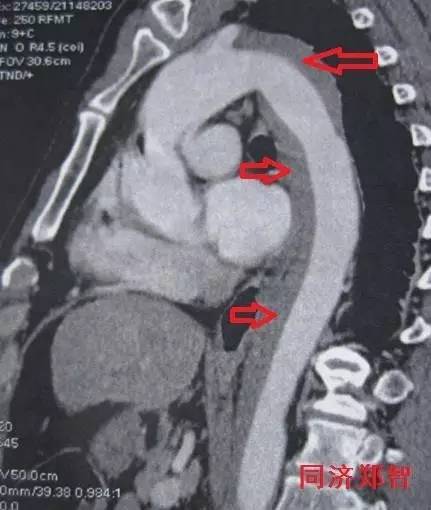

① Stanford B型 主动脉壁间血肿的CTA重建(图1),提示胸降主动脉以远的主动脉壁病变(红箭头所示)。

图1